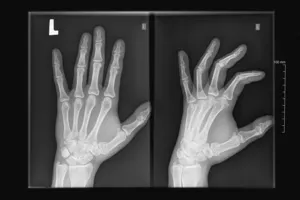

손가락 관절염이 진행되면서 관절 구조에 변화가 생겨 관절이 비뚤어지거나 혹이 생기는 등 변형이 발생할 수 있습니다.